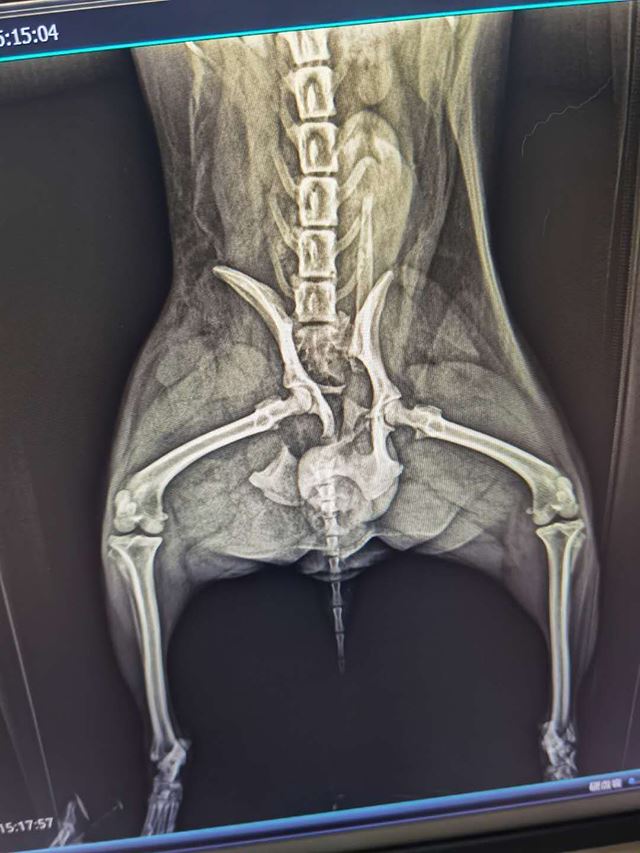

宠物医院的CT检查结果让小哥酸楚,狗狗的伤势很严重,三断:腰椎断,腿断,尾巴断,下半身淤紫一片。凭医生经验诊断:1.要么尽快手术,否则下半身瘫痪了将永远无法站立;2.CT看不出神经是否受损,如果脊椎总神经已损或断,做脊椎接骨手术也是劳而无用,站不起来,手术费白扔。3.要么送苏州宠物医院做MRI后,确定神经受损情况再决定是否手术。